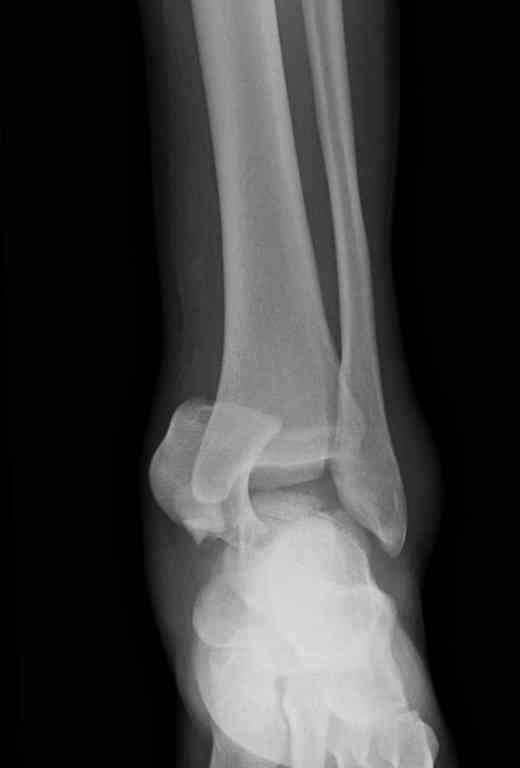

Здесь на фото примеры:

Переломовывих тарана с повреждением медиальной стороны. Через 4 часа после поступления проведена репозиция и фиксация тарана после Irrigation&Debridment. Частичное несращение медиальной лодыжки не беспокоит, вернулся к активному образу жизни. Полная нагрузка разрешена через 11 недель. Финальные снимки через 11 месяцев.